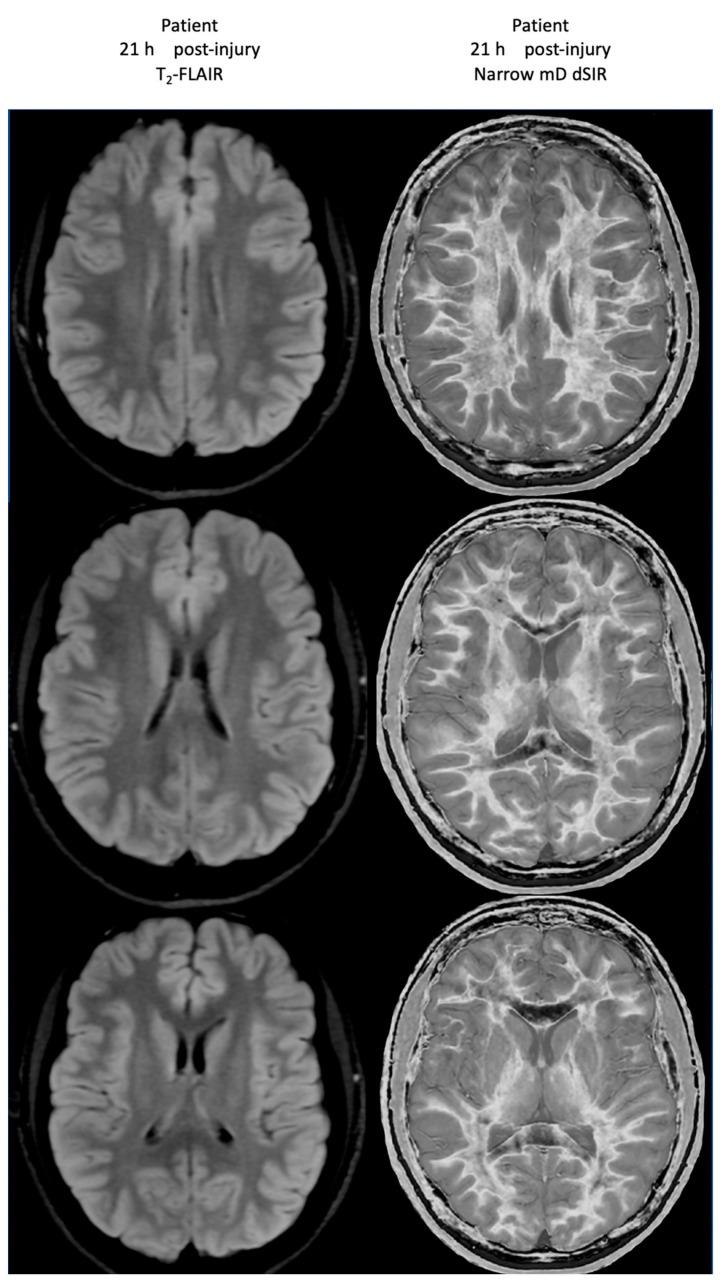

Ultra-high contrast (UHC) MRI describes forms of MRI in which little or no contrast is seen on conventional MRI images but very high contrast is seen with UHC techniques. One of these techniques uses the divided subtracted inversion recovery (dSIR) sequence, which, in modelling studies, can produce ten times the contrast of conventional inversion recovery (IR) sequences. When used in cases of mild traumatic brain injury (mTBI), the dSIR sequence frequently shows extensive abnormalities in white matter that appears normal when imaged with conventional T-fluid-attenuated IR (T-FLAIR) sequences. The changes are bilateral and symmetrical in white matter of the cerebral and cerebellar hemispheres. They partially spare the anterior and posterior central corpus callosum and peripheral white matter of the cerebral hemispheres and are described as the whiteout sign. In addition to mTBI, the whiteout sign has also been seen in methamphetamine use disorder and Grinker's myelinopathy (delayed post-hypoxic leukoencephalopathy) in the absence of abnormalities on T-FLAIR images, and is a central component of post-insult leukoencephalopathy syndromes. This paper describes the concept of ultra-high contrast MRI, the whiteout sign, the theory underlying the use of dSIR sequences and post-insult leukoencephalopathy syndromes.

超高对比(UHC)MRI 描述了这样一些 MRI 形式,在常规 MRI 图像上几乎没有或没有对比,但在 UHC 技术中可以看到非常高的对比。其中一种技术使用分裂相减反转恢复(dSIR)序列,在建模研究中,该序列可以产生比常规反转恢复(IR)序列高十倍的对比度。当用于轻度创伤性脑损伤(mTBI)时,dSIR 序列经常在白质中显示出广泛的异常,而在使用常规 T 液衰减反转恢复(T-FLAIR)序列成像时,白质看起来正常。这些变化在大脑和小脑半球的白质中是双侧对称的。它们部分保留了前中央和后中央胼胝体以及大脑半球的外周白质,被描述为“白化征”。除了 mTBI 之外,在没有 T-FLAIR 图像异常的情况下,该白化征也出现在苯丙胺使用障碍和 Grinker 髓鞘病(缺氧后迟发性白质脑病)中,是创伤后白质脑病综合征的一个核心组成部分。本文描述了超高对比 MRI、白化征、dSIR 序列使用的理论以及创伤后白质脑病综合征的概念。